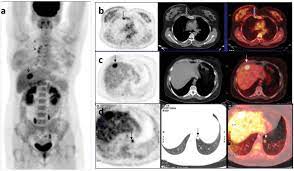

With cancer cells, they appear as bright spots due to its higher metabolic rate compared to normal cells. It is common for patients to receive a diagnosis for cancer of unknown primary. With that being said, not all cancers can be detected by pet. This substance is often called a tracer, because it helps reveal cancer in the body. Each has its own strengths.

For cancer, pet is especially useful as it can scan the entire body and pinpoint both a primary tumor and areas of metastasis (where the cancer has spread).

The test has only a limited ability to detect small tumors. Pet scan for breast cancer a positron emission tomography (pet) scan is an imaging test that uses a radioactive substance (called a tracer) to look for potential spread of breast cancer. In some instances, cancers may not show on the scan. Combining a pet scan with an mri or ct scan can help make the images easier to interpret. Pet scans can be used to determine how much cancer is in a person's body and how far the cancer has spread, which is called staging. This tracer can help identify areas of cancer that an mri or ct scan may miss. With cancer cells, they appear as bright spots due to its higher metabolic rate compared to normal cells. However, the pet scan uncovers every unusual activity in the body and is more sensitive than any other existing imaging test. Pet/ct scan can accurately localize lymph node metastasis and help to monitor the response to chemotherapy. Breast positron emission tomography (pet) scan is an imaging test that uses a tracer (radioactive substance) to look for symptoms of breast cancer. Pet scans can also help to assess whether metastatic breast cancer is responding to the treatment. Pet scans are not used to screen women for breast cancer. Pet/ct scans using axumin tracer, approved by fda last year and newly approved by medicare in some areas, are starting to be done at different locations.

The Clinical Utility Of Fdg Pet Ct In Follow Up And Restaging Of Breast Cancer Patients Sciencedirect from ars.els-cdn.com Pet scan is a type of test that may be used in cancer treatment. A ct scan produces multiple images, providing a detailed picture of the internal anatomy, including the location of cancerous growths. If you have a large breast cancer, your doctor may order a ct scan to assess whether or not the cancer has moved into the chest wall. This substance is often called a tracer, because it helps reveal cancer in the body. It is similar to a pet scan, but it uses a different radioactive substance that settles in areas of change in the bones. For cancer, pet is especially useful as it can scan the entire body and pinpoint both a primary tumor and areas of metastasis (where the cancer has spread). In some instances, cancers may not show on the scan. When breast cancer cancer spreads.

It is common for patients to receive a diagnosis for cancer of unknown primary. Types of cancer detected and treated. Its supposed to be more sensitive/specific than naf and other older scans, and comparable i think to choline or acetate (lots of studies and info on the web) and. With that being said, not all cancers can be detected by pet. A breast pet scan is often very specific and sensitive and is approved for patients. Although it is not appropriate for all patients with breast cancer, fdg pet/ct can have an important clinical effect for appropriate patients. Normally, a pet scan is not used for breast cancer screening. With cancer cells, they appear as bright spots due to its higher metabolic rate compared to normal cells. When breast cancer cancer spreads. Each has its own strengths. For cancer, pet is especially useful as it can scan the entire body and pinpoint both a primary tumor and areas of metastasis (where the cancer has spread). This test can help show if the cancer has spread to your bones. One example is a combined pet and ct scan (known as pet/ct), available in some centers.

Mammograms take advantage of the fact that most of the female breast is fat tissue, so it's relatively transparent to the low doses of radiation used in mammography. Am wondering if all the while we are getting ct scans for lung cancer, is this also scanning for. This test can help show if the cancer has spread to your bones. Normally, a pet scan is not used for breast cancer screening. This radioactive tracer can help identify areas of cancer that an mri or ct scan may miss. In conclusion, this case shows that pet/ct can be utilized as an alternative method of diagnosing breast cancer in cases where conventional imaging modalities fail. The report of ct scan cannot be the basis of determining if a patient has cancer or not; A pet scan is often combined with a ct scan (known as a pet/ct scan). Right now, ct scans are not used routinely to evaluate the breast. This tracer can help identify areas of cancer that an mri or ct scan may not show. A breast pet scan is often very specific and sensitive and is approved for patients. Objectives bone is the most frequent site of breast cancer metastases.considering many breast cancer patients are old age,bone is likely affected by degenerative or inflammatory bone disease.recently pet/ct has become an alternative study which could provide an accurate and efficient tool for detection of primary and metastatic foci.the purpose of this study was to compare the accuracy between pet/ct and bone scan for detecting bone metastases in breast cancer. In a ct scan, you can see the broad pictures of all tissues and organs present in the body.